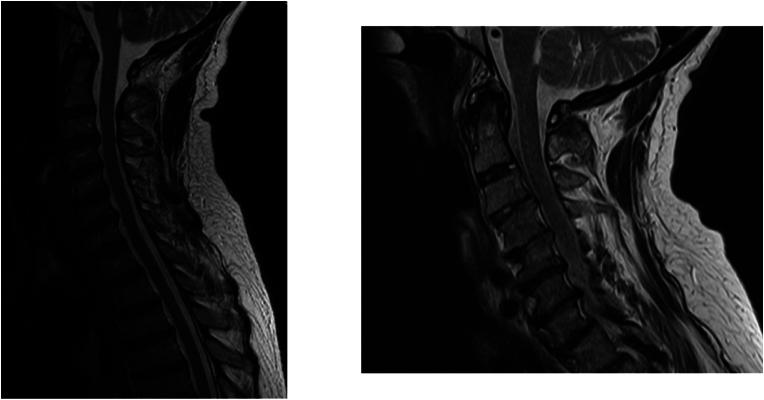

Patients with RA in which follow-up cervical MRI studies (at least 3 years apart) were available were identified retrospectively in two tertiary care centers. Patients without definitive deformity at baseline were included in the algorithm. Patients were assessed for RA-associated cervical spine deformity, defined as presence of pannus and/or degeneration of the facet joints of C0-C1 and/or C1-C2 on follow up MRI.

A deep learning model was developed to predict the development of pannus and/or facet joint deformity at the craniocervical junction of patients with RA. Future research should focus on large-scale validation of this model with diverse sites and identifying the role of the subaxial spine in the risk of deformity at the level of the craniocervical junction during the course of disease.